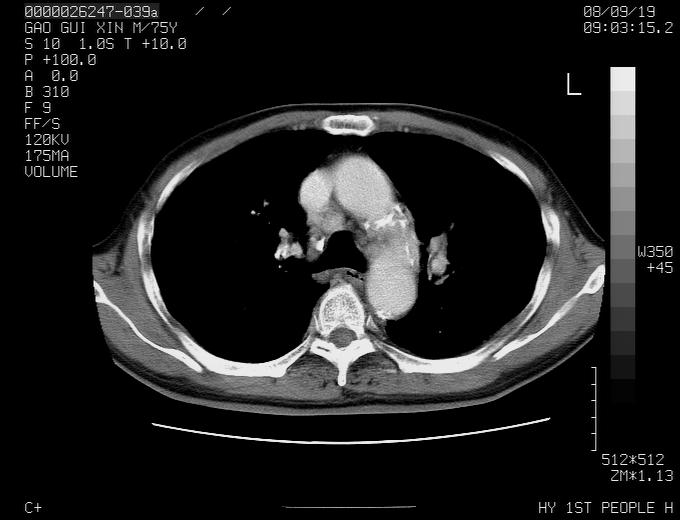

感谢各位老师的意见,左上肺病灶,我本人趋向结核,原因:左上肺见两个类圆形结节,仔细回顾4月份ct似乎原片在该处有条片状密度增高影,强化不明显。

现上传增强片,请各位老师仔细帮我看一下。

右上肺可见条索状影,并可见钙化,左上肺结节可以考虑为结核球,但气管前腔静脉后有肿大淋巴结,本人觉得左上肺结节不能排除转移瘤的可能,右上肺为陈旧性结核灶。

左肺上叶周围性肺癌并纵隔多组lnm.不可能是tb.

左肺上叶尖段瘢痕癌并纵隔淋巴结转移解释更好一些.

1)左肺上叶尖段周围型肺癌并纵隔淋巴结转移。2)冠状动脉及主动脉钙化。